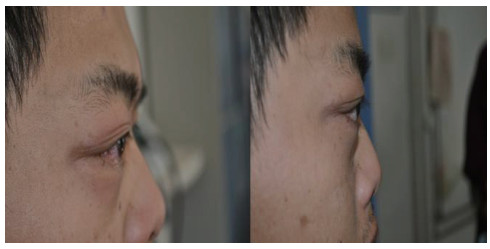

2.1 临床表现本研究中CCF患者出现眼球突出141例(97.91%)、球结膜充血140例(97.22%)、颅鸣105例(72.92%)、视力下降99例(68.75%)以及复视36例(25.00%)症状,见图 1。查体可见眼球突出、球结膜充血水肿,眼球运动障碍;眶周可闻及血管杂音,Matas试验阳性。脑部血管影像学检查,全部患者可见眼部静脉异常增粗[8],见图 2。

| 图 1 治疗前后右眼眼球突出和球结膜充血情况对比 Fig 1 Comparison of proptosis and bulbar conjunctival hyperemia of right eye before and after treatment |

颈内动脉海绵窦瘘经介入栓塞治疗后,颅内杂音立即消失,数小时后球结膜充血水肿明显好转,1周后眼球突出可恢复正常。在3个月的随访中,本研究中术后出现复发共15例,1个月以内复发12例,2个月内复发3例,复发率10.42%。对年龄、性别、受伤至治疗时间、术前眼压、术后眼压与3个月总体复发情况进行Logistic回归分析显示,术后眼压是提示患者复发的独立危险因素(P<0.05),见表 2。